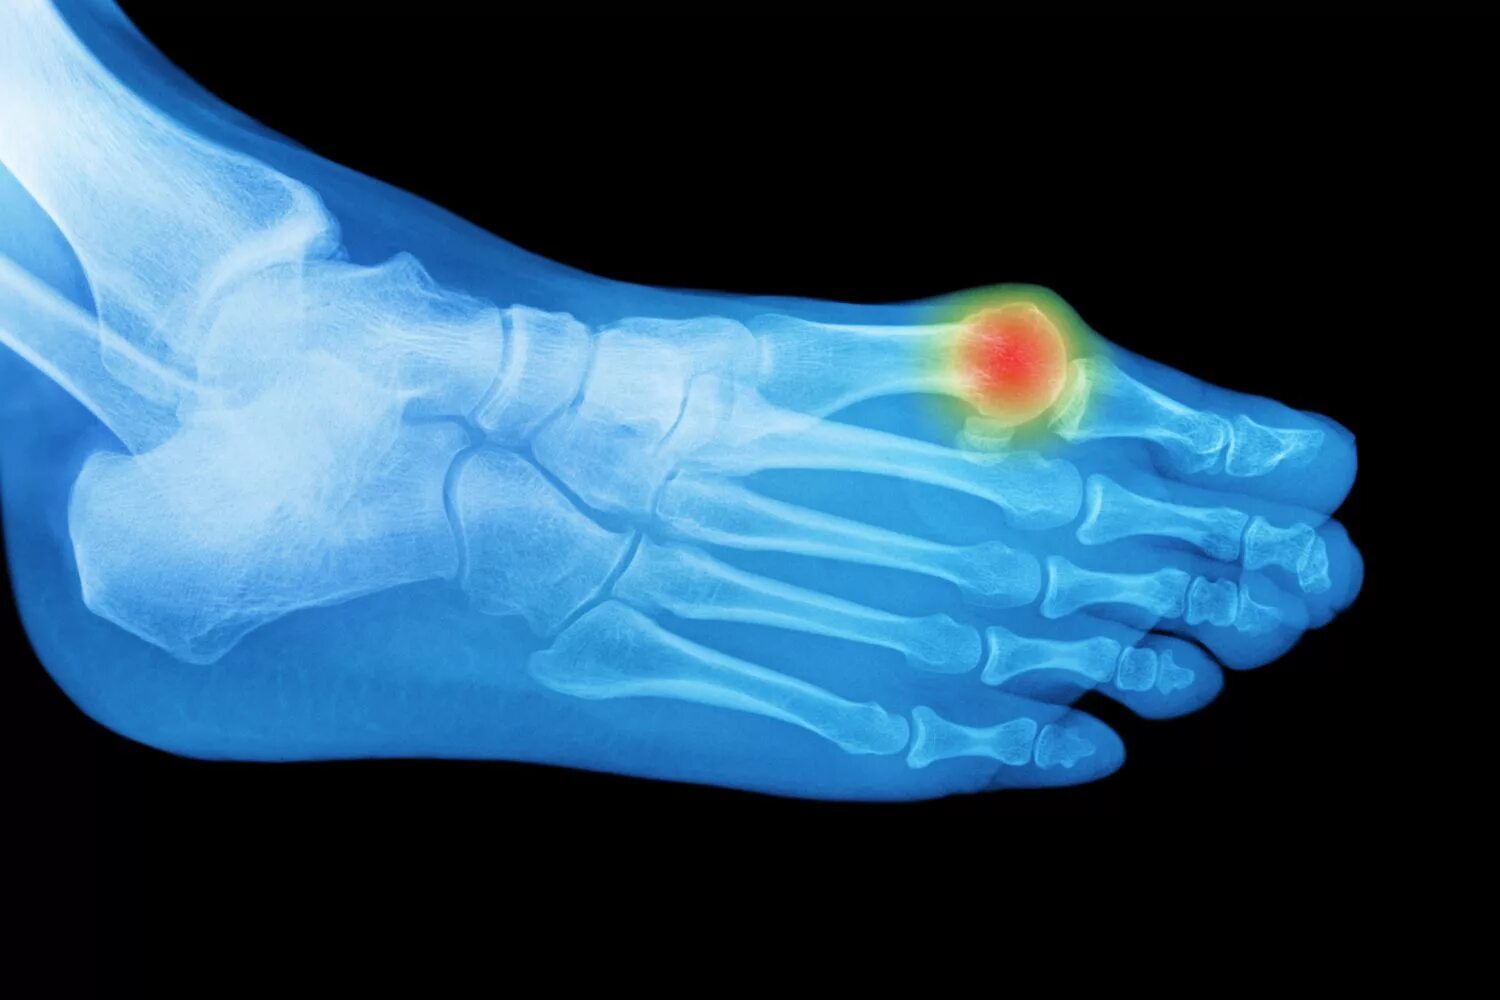

Артроз плюснефалангового сустава стопы